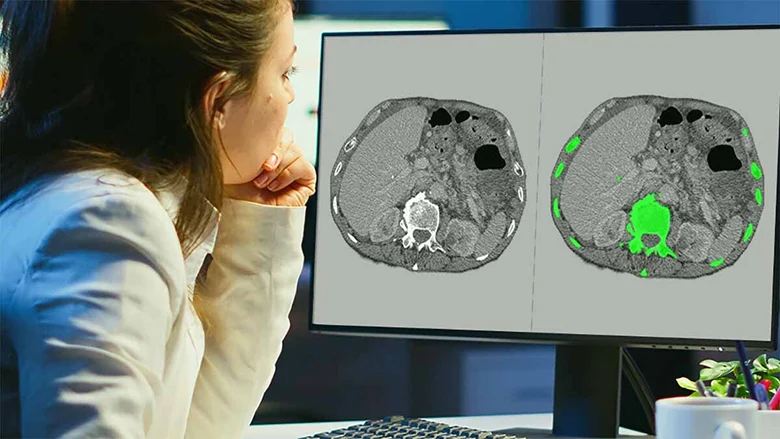

Medical image segmentation, on the other hand, goes a step further. Instead of simply identifying what exists, segmentation defines exactly where it exists—often down to individual pixels in 2D images or voxels in 3D scans like CT and MRI. This level of precision is critical for clinical applications where boundary accuracy directly affects model outcomes.

- Semantic segmentation: Classifies every pixel into a predefined category, useful for identifying broader anatomical regions.

- Pixel-level / Voxel-level segmentation: Provides high-precision boundaries essential for detecting subtle abnormalities and measuring progression.

- 3D volumetric segmentation: Applied to CT and MRI data, enabling spatial understanding across slices rather than isolated images.